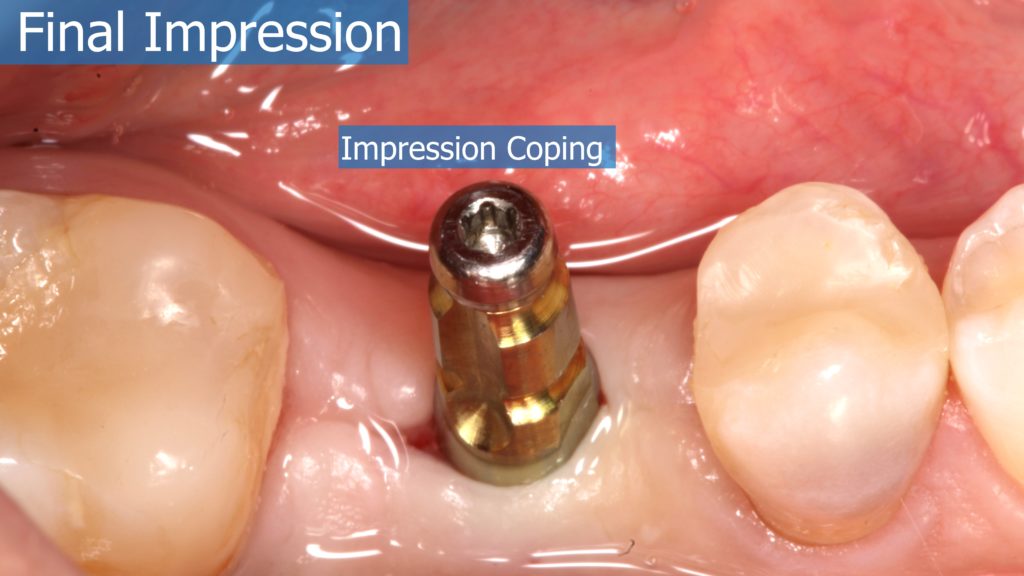

A healthy 36 year old woman comes to the clinic with pain and swelling in the area of the inferior left molars. In the intraoral observation, a vestibular fistula was identified, and the complementary exams confirmed a bone lesion caused by a root perforation (poorly executed false post) on the first lower left molar #36 (19). It was decided to do antibiotic therapy for a week and then the tooth extraction with immediate implant placement and bone graft. 4 months post-op the definitive zirconia/ceramic crown would be was made.